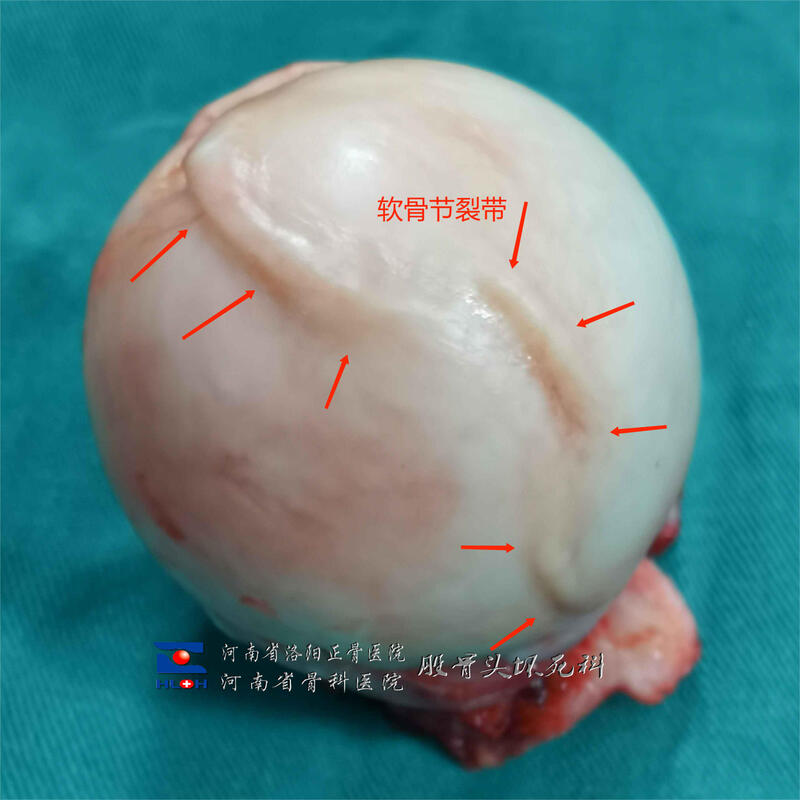

箭头所示隆起的“软骨脊”其实就是塌陷以后造成的,犹如地壳剧烈运动形成的山峰。

箭头所示区域即为坏死骨,可见坏死骨和软骨下骨已经整体剥离。